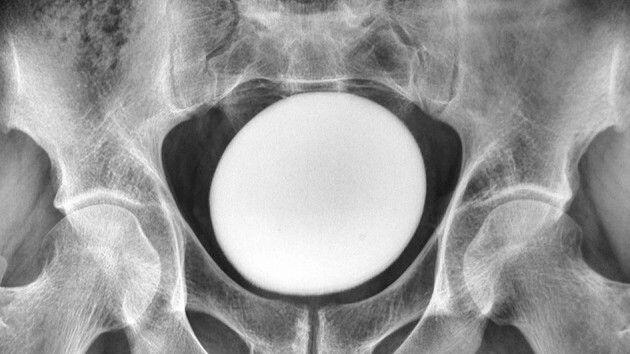

The Signal Wire

Breaking News - Health Talk - When Normal Oxygen Levels Mask a Deeper Crisis Today’s Signal Wire feature examines a medical case that challenges one of healthcare’s most trusted metrics. Oxygen saturation: Normal. Lungs: Clear. Cardiac function: Stable. Laboratory findings: Unremarkable. Yet the patient was gasping for air. When supplemental oxygen was administered, saturation levels declined rather than improved. This is not routine variation. This is a signal disruption. Cases like this move medicine from protocol to pattern recognition. Several physiological explanations may account for this anomaly: Dyshemoglobinemia Toxic Environmental Exposure Cellular Hypoxia Equipment–Environment Interaction This case highlights a critical truth in modern medicine: Data points are measurements not conclusions. As healthcare integrates artificial intelligence, wearable biometrics, and predictive modeling, the volume of available data continues to grow. However, signal interpretation remains essential. When multiple individuals in a shared environment experience physiological distress, the pattern itself becomes clinically significant. This is not merely a patient event. It is a potential signal cluster. But predictive systems depend on recognizing when data appears normal while physiology is not. Sometimes oxygen is present. But the system is not functioning. That distinction can determine outcomes. Follow @thesignalwire for continued Signal Wire briefings analyzing the patterns reshaping modern healthcare. #BreakingNews #getinspired #Inspiration #HealthNews #thesignalwire #NewsBreaks #Mystery #MedicalMystery #AI